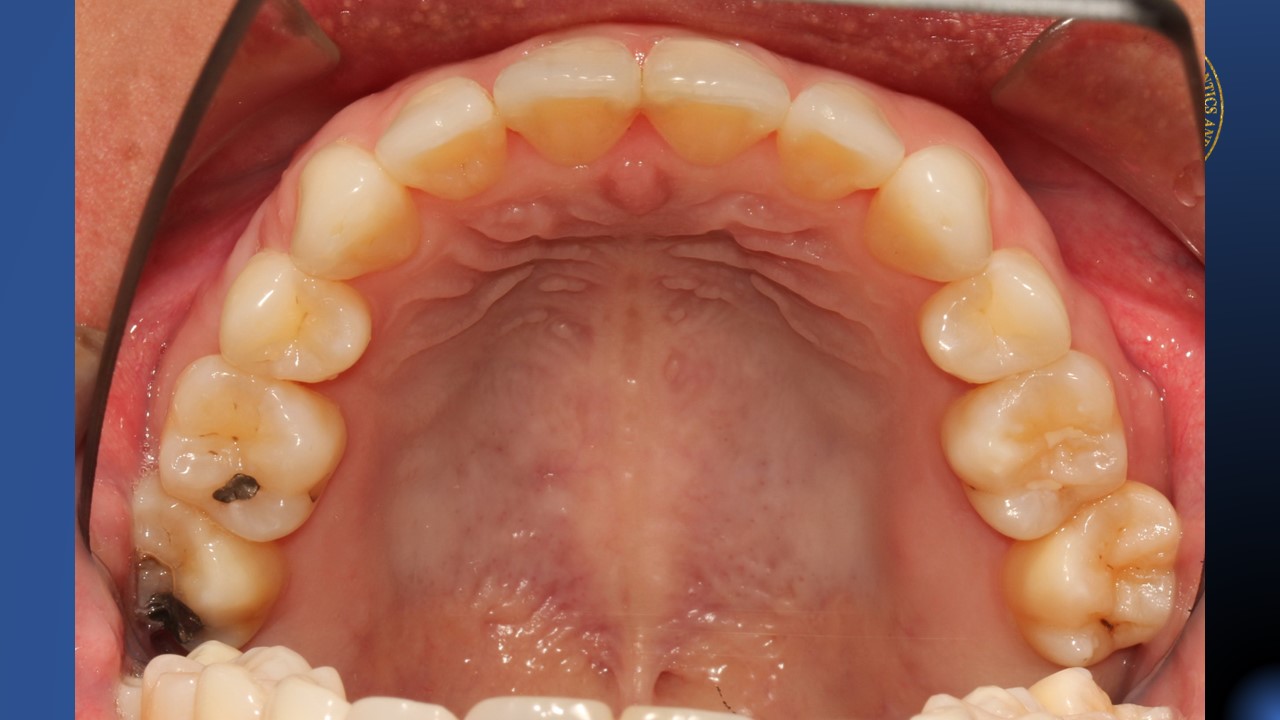

- Lack of knowledge in Periodontology. Treating a patient over the age of 30, the risk of horizontal alveolar bone loss is great as the orthodontic force is applied and regeneration power is decreased

- Treating a patient over the age of 30, the tooth extraction must be avoid.

- Finishing occlusion will be even more than worst. The operator was totally underestimate the side effects of closing 10 mm on the left side and 7 mm on the right side space in the mandible